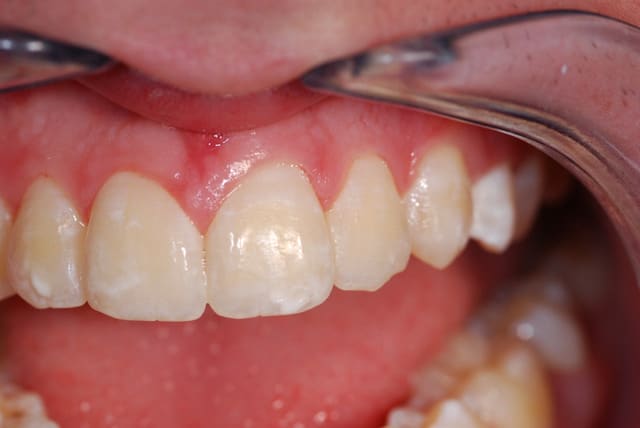

Moi je la trouve pas mal ta photo 3.

Le défaut du flash LED c'est la dominante bleu/désaturé des couleurs mais c'est correct je trouve.

Tiens une photo pas séchée non plus, avec mon capteur sale. Faite au 1:1 il me semble, avec flash annulaire Canon. Moins de reflets mais il y en a quand même.

Le but du flash annulaire c'est de supprimer les ombres portées, du coup on a un risque de reflet sur les surfaces réfléchissantes.